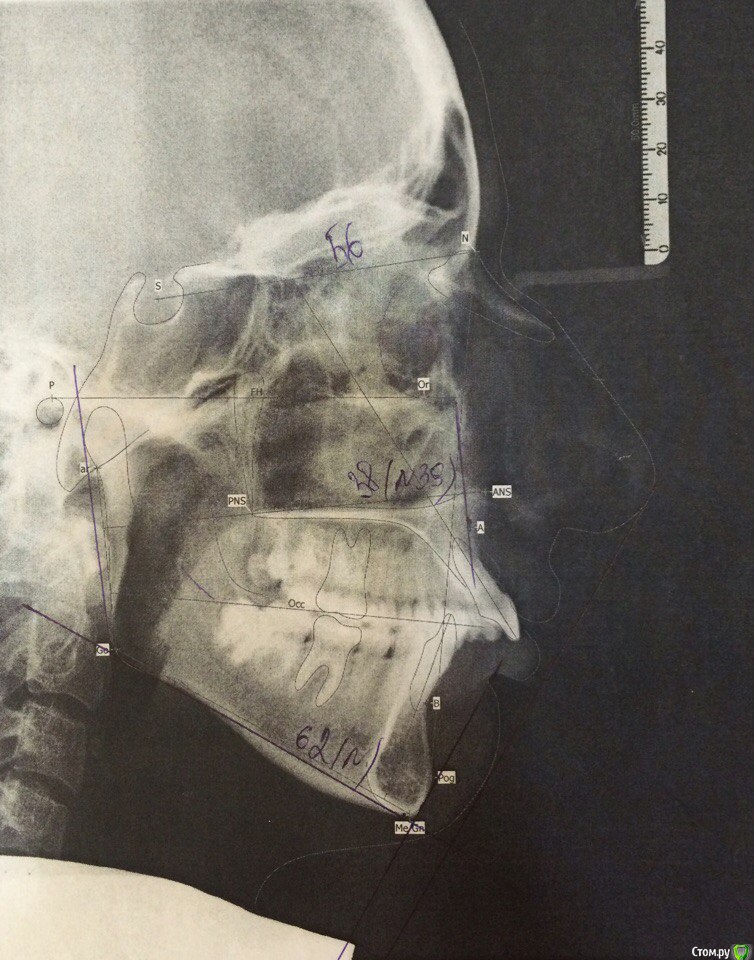

annurka Опубликовано 13 сентября, 2017 Автор Поделиться Опубликовано 13 сентября, 2017 (изменено) вот трг до начала лечения, фото к сожалению нет, если только из жизни) расшифровка трг ДО (где выделено синей ручкой) и недавнее Конечно контакты не идеальны, но если удалить 4ки наверху нижняя треть лица будет иметь довольно вогнутый вид спасибо за комментарий! а если сделать сепарацию резцов, тогда получится избежать вогнутости профиля? С ДВНЧС у вас сейчас проблемы остались? Можно рассмотреть совместно с врачом аппараты для выдвижения нижней челюсти,если тяги не справляются не было до недавнего времени - сейчас иногда болит в области сустава слева (видимо потому что контакты справа уже есть, а слева в процессе, поэтому нагрузка на челюсть неравномерная ?). до операции (но после начала лечения брекетами) сустав не беспокоил, надеюсь это просто период реабилитации.насчет аппаратов по выдвижению НЧ - спасибо, передам ортодонту.с6нимки к сожалению выполнены в разных клиниках, но мне казалось что если судить по трг через полгода, то НЧ там же, где была закреплена титановыми пластинами сразу после остеотомии (но проблема с резцами тогда уже возникла)... или мне так только кажется и произошел рецидив? думаете ее можно еще двинуть вперед? Изменено 13 сентября, 2017 пользователем annurka Ссылка на комментарий

annurka Опубликовано 14 сентября, 2017 Автор Поделиться Опубликовано 14 сентября, 2017 (изменено) Нет, я трг пока не могу рассчитать, чтобы это утверждать - на выходных только время будет, а пока с телефона смотрю. Предполагаю,да.Ну и плюс контакты зубы ищут правильные и смыкаются в разном положениивообще к обоим трг (до и нынешнее) я добавила расшифровку выше, или вы имеете ввиду те, что с титановыми конструкциями? мне все же хочется верить что это с зубами беда, и они новой челюсти не подходят, а не то что челюсть куда-то съехала.. в принципе, как и любому человеку, пережившему перемещение двух челюстей. еще есть такое фото, сделала его сразу после операции, швы не позволяли толком губы раскрыть, а рот нельзя было открывать на протяжении месяца, поэтому такое качество: http://i12.pixs.ru/thumbs/5/6/2/w1BZH71BWi_3410341_27523562.jpghttp://i12.pixs.ru/thumbs/5/5/3/4pJjOEAIq2_4300116_27523553.jpg там видно, что резцы сходятся как следует, а больше никаких контактов нет у других зубов. эластик (который скреплял от движения челюсть) в то же время создавал контакты клыков, носила только их месяца 4. фото через месяц после оп, тенденцию верхних резцов уже видно (но рот мне еще открывать нельзя было)http://i12.pixs.ru/thumbs/6/4/3/IMG5512JPG_8912889_27523643.jpghttp://i12.pixs.ru/thumbs/6/3/1/4pJjOEAIq2_7818185_27523631.jpghttp://i12.pixs.ru/thumbs/6/4/9/IMG5522JPG_8755357_27523649.jpghttp://i12.pixs.ru/thumbs/6/5/1/IMG5525JPG_1306296_27523651.jpg спустя 2 месяца после оп, стала жевать еду, открывать рот могла только на 2смhttp://i12.pixs.ru/thumbs/6/5/7/IMG9072JPG_6555113_27523657.jpghttp://i12.pixs.ru/thumbs/6/6/5/IMG9080JPG_2398494_27523665.jpghttp://i12.pixs.ru/thumbs/6/7/3/IMG9085JPG_1231417_27523673.jpg по ссылке доступно увеличенное изображение, спасибо Skip Изменено 14 сентября, 2017 пользователем annurka Ссылка на комментарий